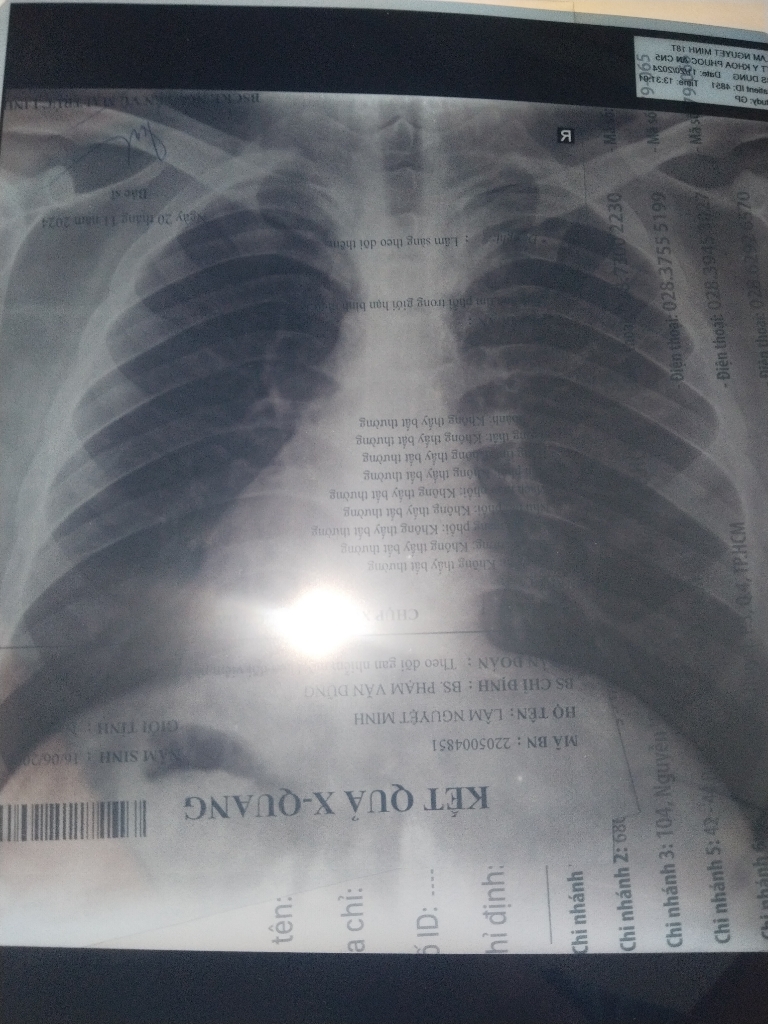

Chào em. Em nên chụp x quang phổi kiểm tra nhé

Kiểm tra có vấn đề phổi gây ho máu không

Em đi khám chụp x quang rồi không có vấn đề